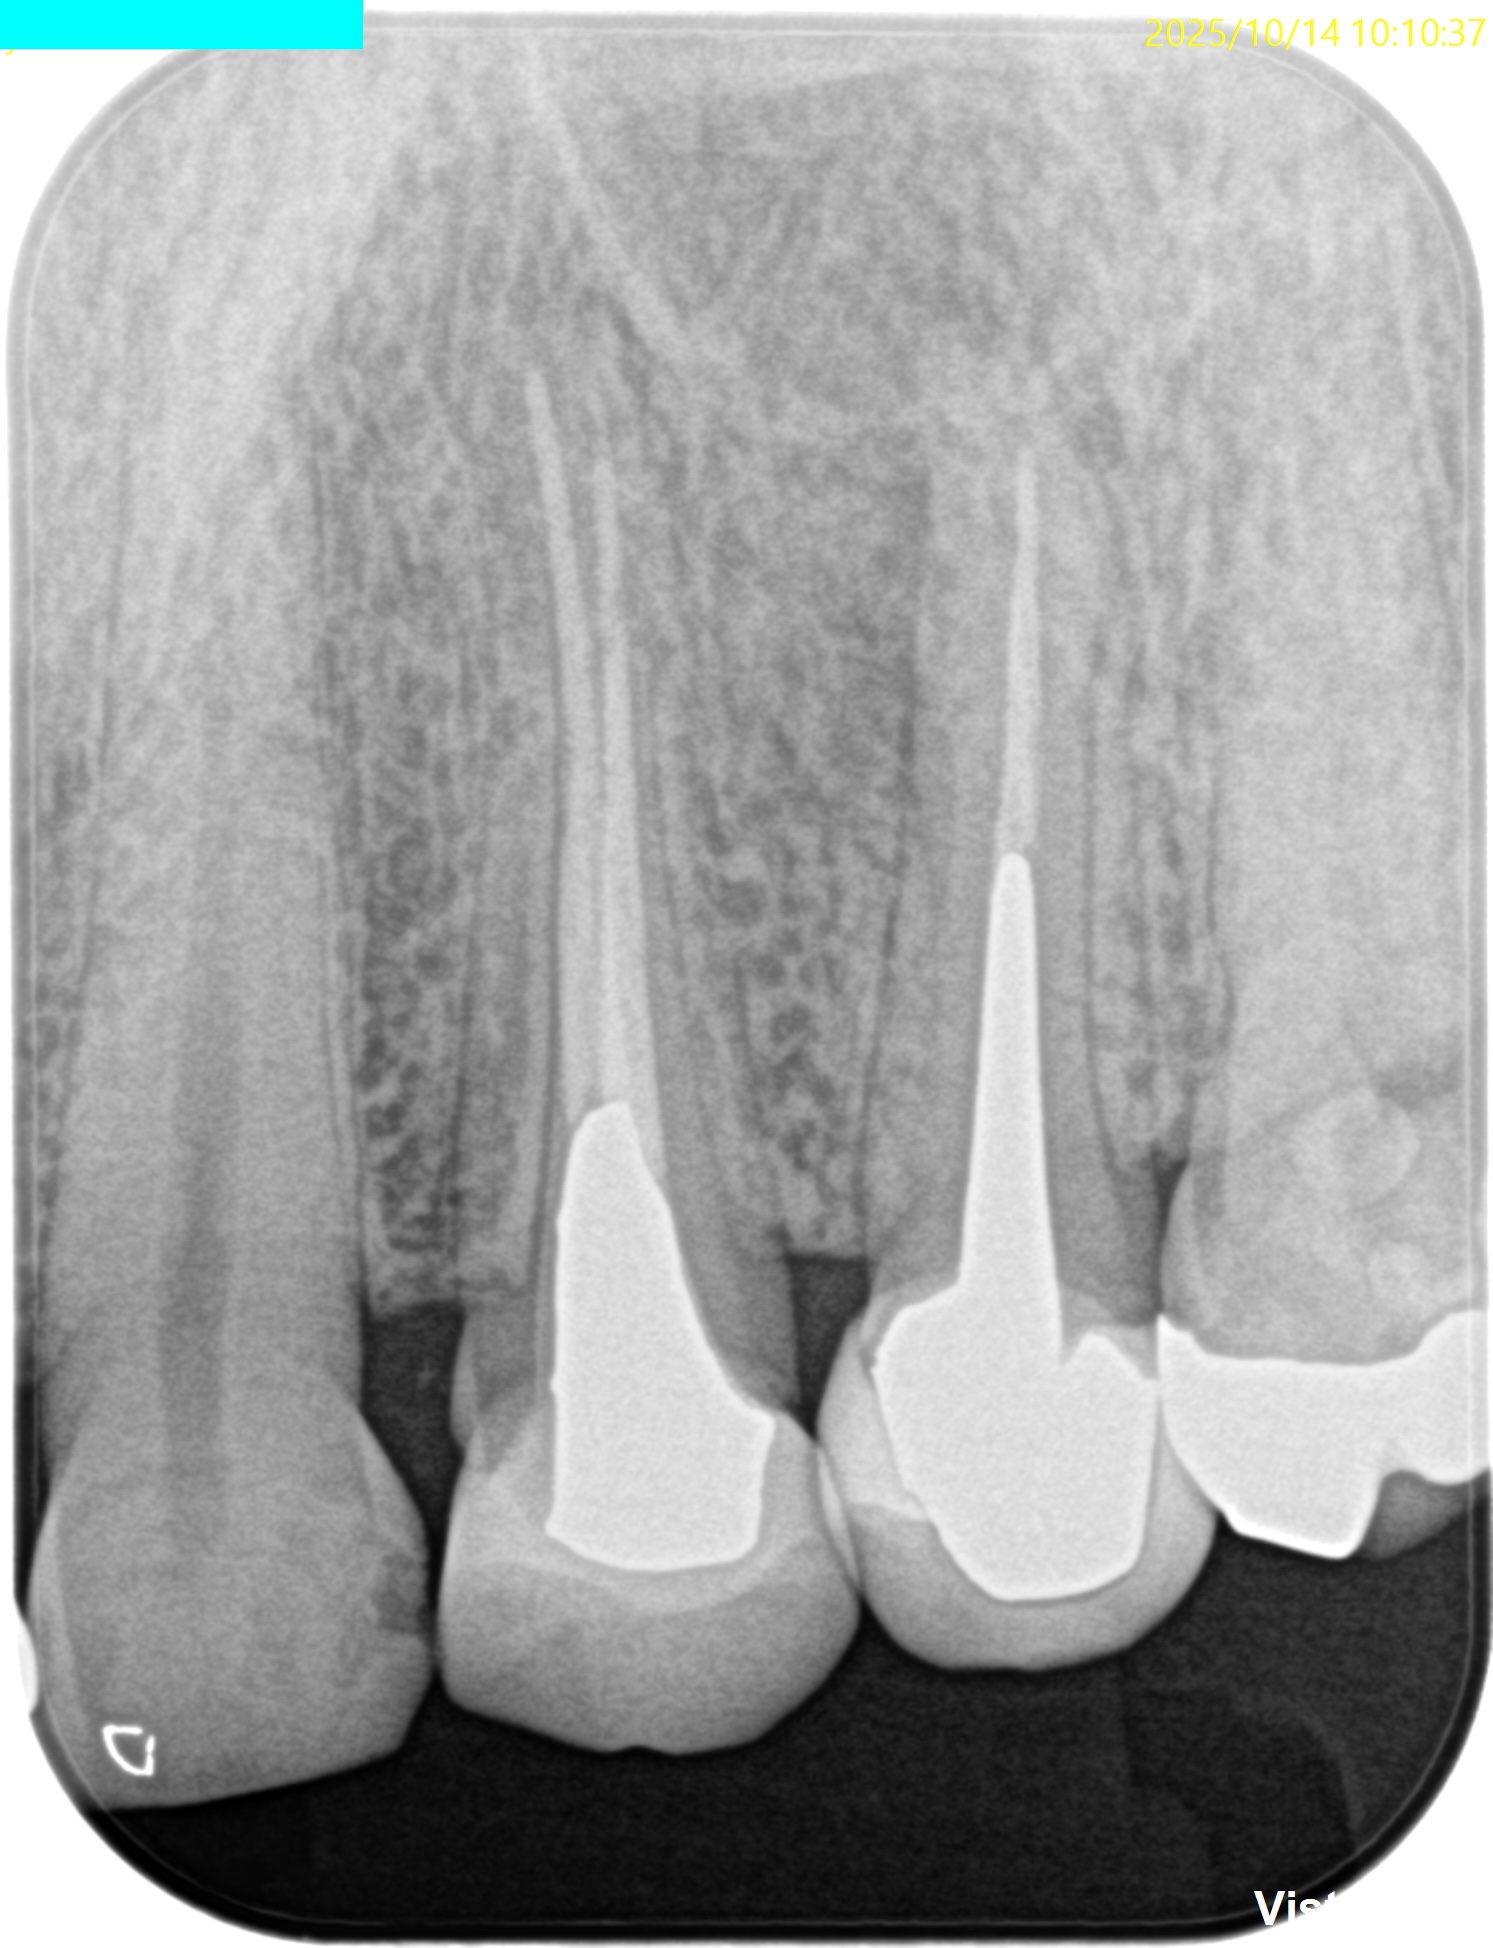

PA(2025.8.25)

#13のポストは長くテーパー型だが除去には時間を要するだろう。